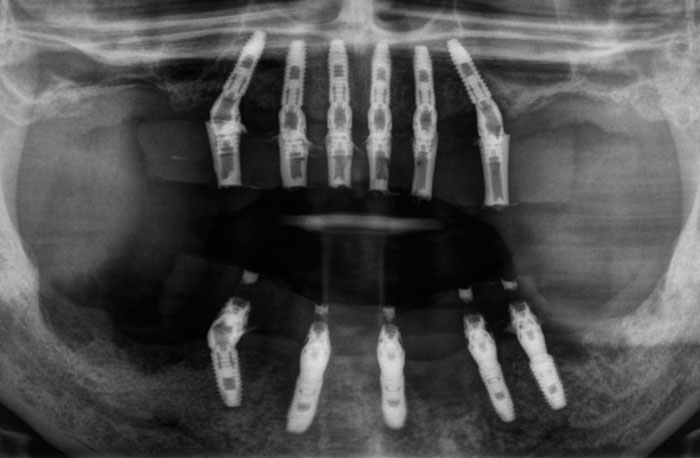

インプラント埋入後のレントゲン写真

全ての残存歯の抜歯と同時に上下11本のインプラントを埋入して、その後すぐに事前に作成しておいた仮歯を装着しました。歯がない期間が全くないので、生活に支障なくインプラントで固定された歯を使いながらインプラントと骨が結合する期間を待つことができます。

インプラントを埋め込んでから約6ヶ月後に型取りを行なって最終の歯を製作して装着しました。治療前の状態に比べて、骨に支えられたしっかりした歯で何でも美味しく食事ができるようになったと患者様も喜ばれておられました。